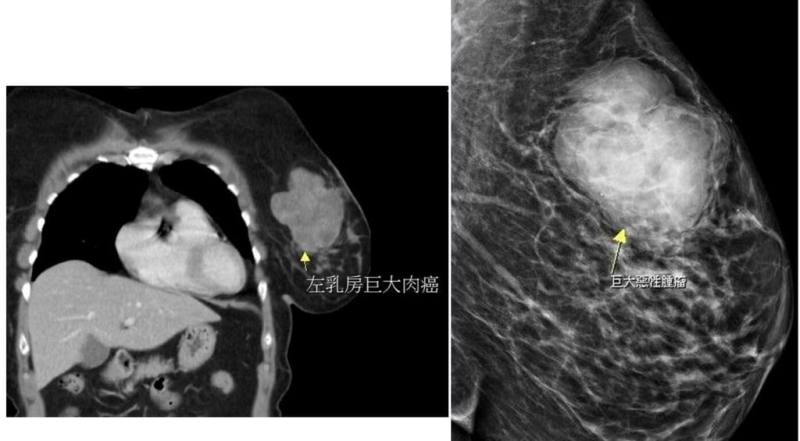

苗栗有婦人單側乳房出現硬塊,就醫檢查出近10公分大腫瘤,手術切除病理報告並非臨床常見的乳腺癌,而是發生率低且罕見出現在乳房部位的肉癌。(大千綜合醫院提供)

(中央社訊)苗栗有婦人單側乳房出現硬塊,就醫檢查出近10公分腫瘤,手術切除病理報告非臨床常見的乳腺癌,而是發生率低且罕見出現在乳房部位的肉癌,醫師提醒身體有異狀務必儘早就醫。

這名56歲黃姓婦人數月來感到左側乳房摸起來有異狀,起初不以為意,直到近日明顯摸到硬塊而且會疼痛才就醫,經超音波檢查已是將近10公分大的腫瘤,大幅增加治療困難度,所幸術後恢復良好,病理報告也證實腫瘤已切除乾淨,持續密集追蹤狀況。